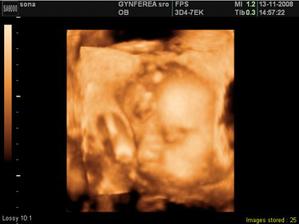

na svet som prišla 29.01.2009 s mierami jak modelka - 50cm a 3300g..Volám sa Sonička a už sa teším na krásny život spolu s maminkou a tatinom :O)